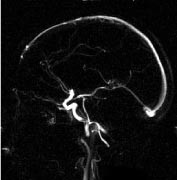

Intrakraniale kar

Kontrastforsterket MRA har foreløpig for dårlig romoppløsning for intrakranialt bruk. Den MRA-metoden som er best egnet for fremstilling av intrakraniale arterier, er 3D-innstrømnings-MRA (fig 3). Ved hjelp av denne metoden kan man påvise stenoser og okklusjoner av de større arteriene. Både MRA og CT-angiografi kan fremstille intrakraniale aneurismer med diameter på 5 mm eller mer med stor nøyaktighet (10, 11), for mindre aneurismer synes CT-angiografi å være noe bedre enn MRA. De ikke-invasive metodene kan bidra ved planlegging av behandling av aneurismer (kirurgisk eller radiologisk intervensjon), men metodene har ennå ikke kunnet erstatte kateterangiografi (12). Ved intrakraniale arteriovenøse malformasjoner er MR-snittbilder den metoden som best viser den anatomiske lokaliseringen av nidus (13). MRA kan gi en bedre anatomisk oversikt over hele malformasjonen, særlig om man benytter fasekontrast-MRA, som gir best fremstilling av både arterie- og venesiden. Både kirurgi og endovaskulær embolisering krever imidlertid en detaljfremstilling som bare kan gis av kateterangiografi.